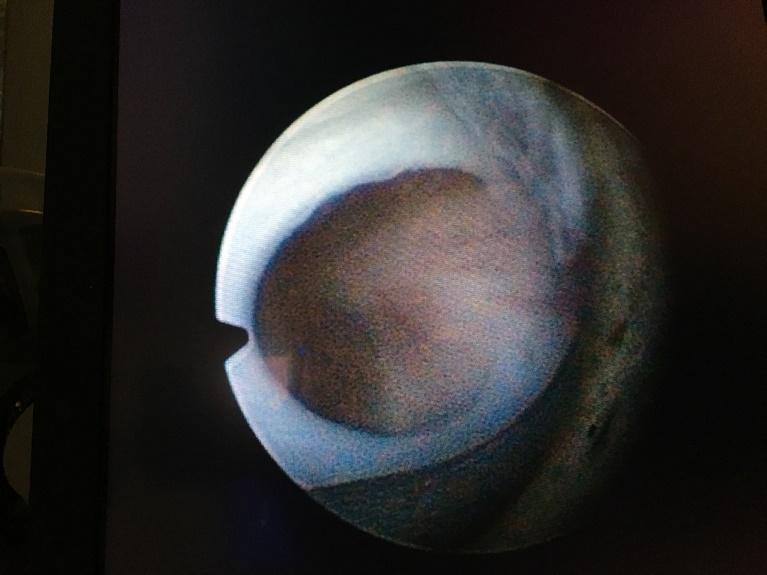

Urethrakleppen ontstaan al zeer vroeg in de 7e à 8e week van de zwangerschap. De vorming van de plasbuis verloopt in dit geval niet helemaal normaal. Aan het begin van de plasbuis blijven vliesjes bestaan in het gedeelte waar zich later de prostaat zal ontwikkelen. Als er plas langs stroomt, bollen deze vliesjes op als de zeilen van een zeilschip. Daardoor wordt de plasbuis nauwer en moet de blaas harder werken om leeg te komen. Als er niet geplast wordt, zakken de vliesjes weer tegen de wand van de plasbuis. Er is dus sprake van een vernauwing in één richting: De klepvliezen bollen alleen op als er geplast wordt. Bij het inbrengen van een katheter (een buisje in de plasbuis tot in de blaas) is er in het algemeen geen probleem want in die richting kunnen de vliezen niet opbollen. Er is altijd sprake van een gedeeltelijke vernauwing en nooit van een volledige stop. Urethrakleppen zijn aangeboren maar niet erfelijk.

Beeld van urethrakleppen bij de kijkoperatie (cystoscopie). De vliezen zitten vast aan de boden en zijwand van de plasbuis en zijn aan het “plafond” van de plasbuis samengegroeid.